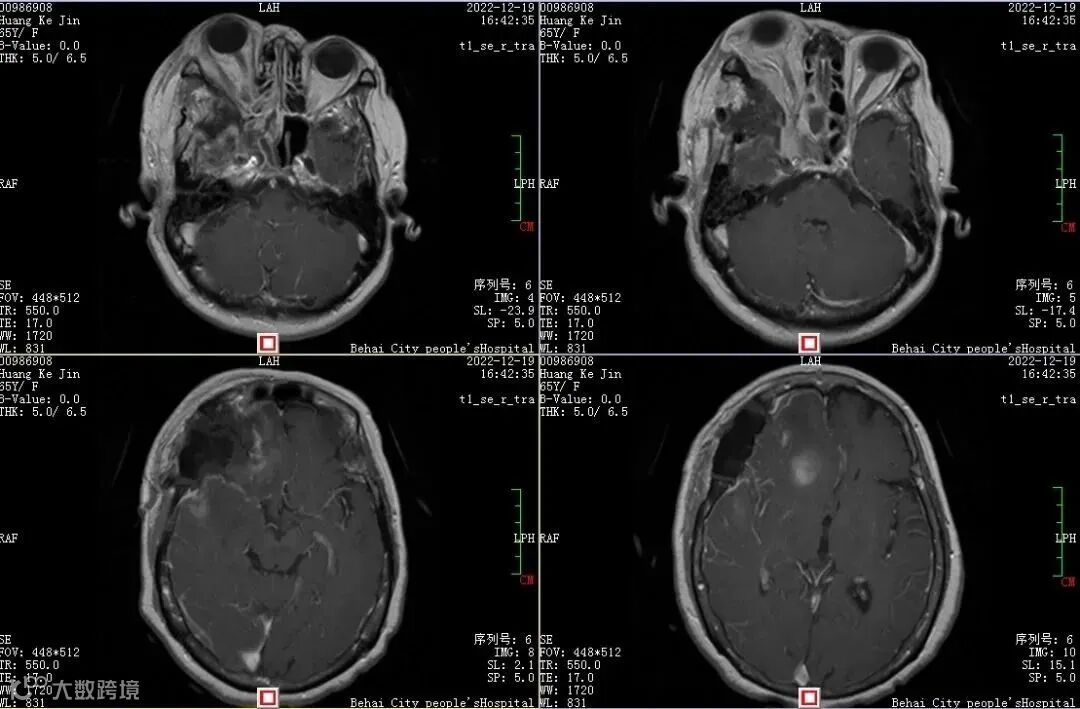

术后1周复查磁共振显示颅内及右侧眶内、蝶窦内肿瘤已切除,突出的右眼球也逐渐回缩。

邓峰介绍,这个良性的颅底沟通脑膜瘤从颅内长到颅外,在临床上相对比较少见,肿瘤在颅底向四周匍匐生长,涉及到颅内以及眼眶、鼻窦,包绕重要血管神经,手术风险高,难度大,最终顺利完成了手术。

术中重建了颅底,术后患者顺利度过了水肿和感染风险,术后病人眼球慢慢回缩,视力还能保留着术前的水平,病人和家属比较满意,康复出院。